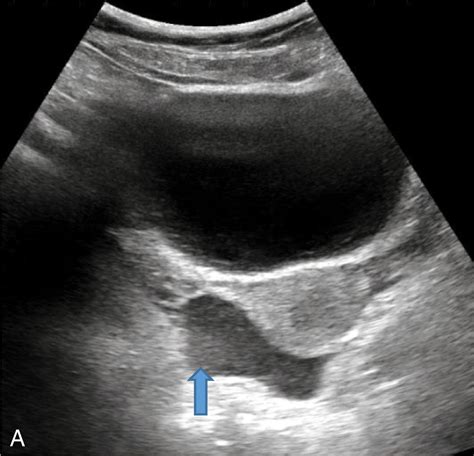

Imaging tests are particularly important in diagnosing Free Fluid in Pelvis. Ultrasound is often the first-line imaging modality due to its non-invasive nature and ability to detect fluid collections. CT scans and MRIs provide more detailed images and can help identify the cause of the fluid accumulation.